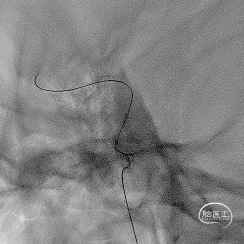

1

前交通开放代偿右侧大脑中动脉。

后循环未向右侧大脑中动脉代偿供血。

病变展示:右侧颈内动脉后交通段次全闭塞。

2.0×9mm球囊扩张,可见残余狭窄较重。